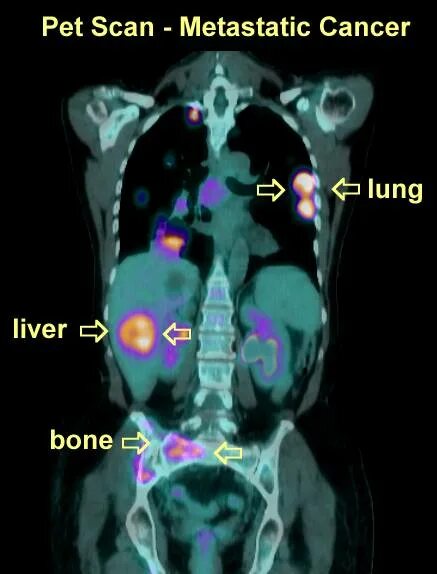

Scan means